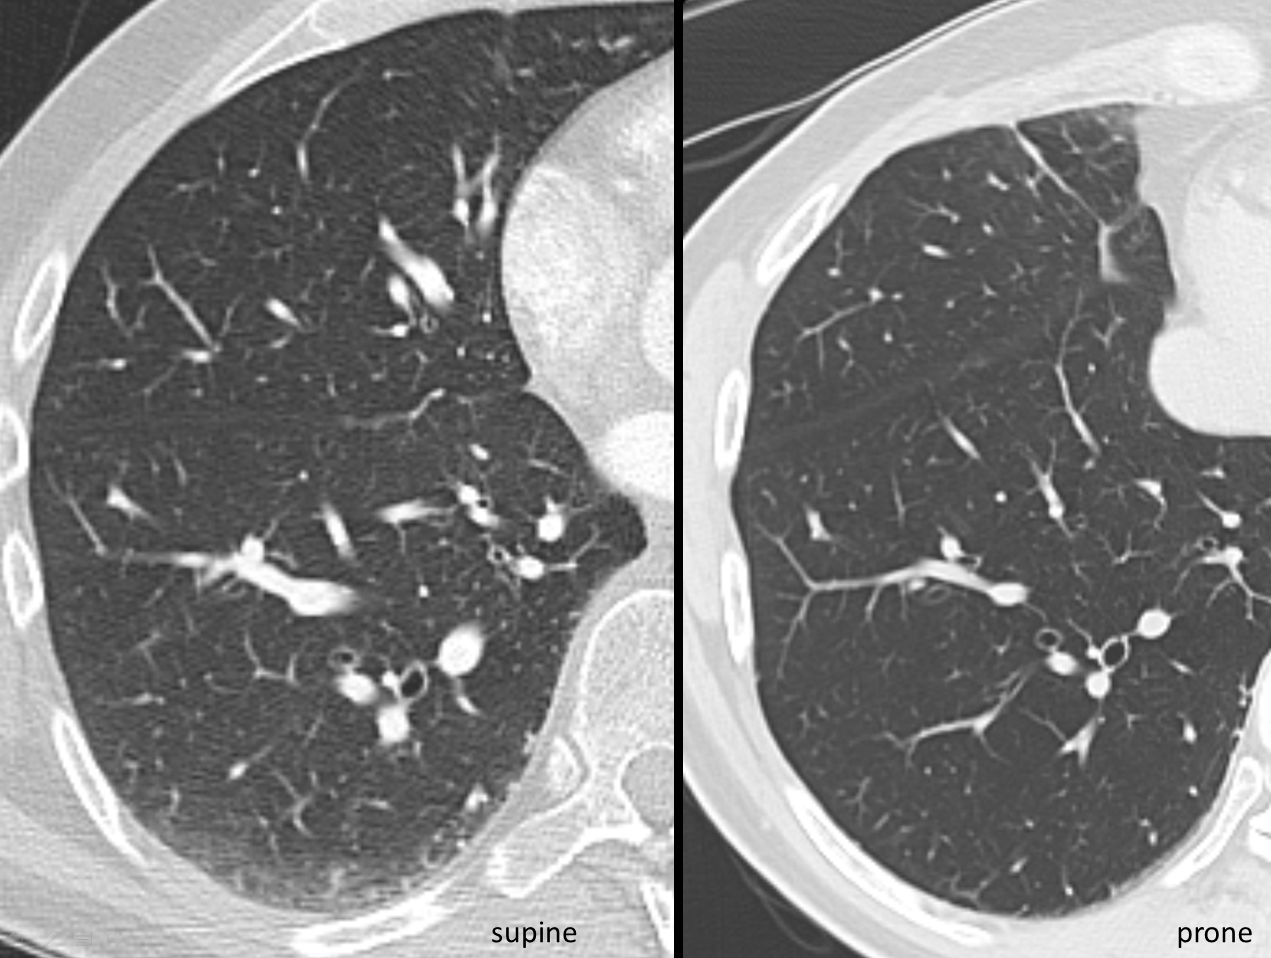

CT supine and prone